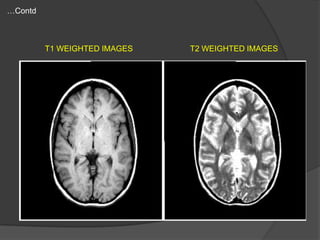

T1 WEIGHTED IMAGES

T2 WEIGHTED IMAGES

T1 Weighted MRI



Best for visualizing normal

neuroanatomy

Sharp boundaries between

grey matter, white matter, and

CSF

Useful in evaluation of

cerebro-pontine angle cistern

& pituitary fossa

Bone white

white matter light grey

grey matter medium grey

water/CSF/air- Black

T2 Weighted MRI

Less distinct boundaries

between white and grey matter

Best for displaying pathology

Useful in demyelination, edema

& tumour infiltration

Gray matter medium gray

white matter dark grey

CSF and water White